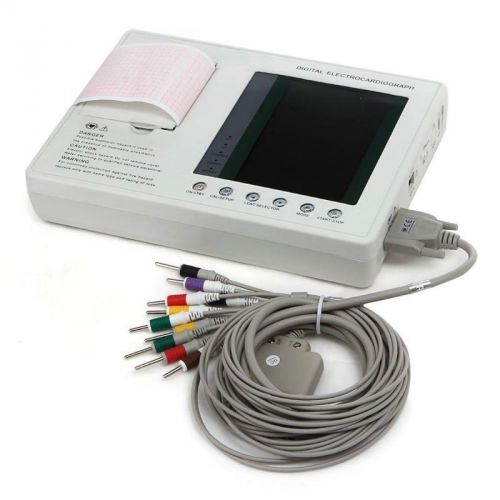

7-Inch Color LCD Digital 3-channel 12-lead Electrocardiograph EKG ECG Machine OO

7-Inch Color LCD Digital 3-channel 12-lead Electrocardiograph EKG ECG Machine UU

7-Inch Color LCD Digital 3-channel 12-lead Electrocardiograph EKG ECG Machine CA

Portable Digital 1-channel Electrocardiograph ECG/EKG Machine*CE *FDA TOP A